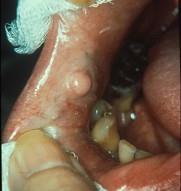

组图为口内纤维瘤的外观,关于此病的描述不正确的是()A.主要由纤维组织构成B.生长一般较缓慢C.肿瘤边界清楚D.手术后不易复发...

问题 组图为口内纤维瘤的外观,关于此病的描述不正确的是()

选项 A.主要由纤维组织构成 B.生长一般较缓慢 C.肿瘤边界清楚 D.手术后不易复发 E.有可能恶变

答案 D